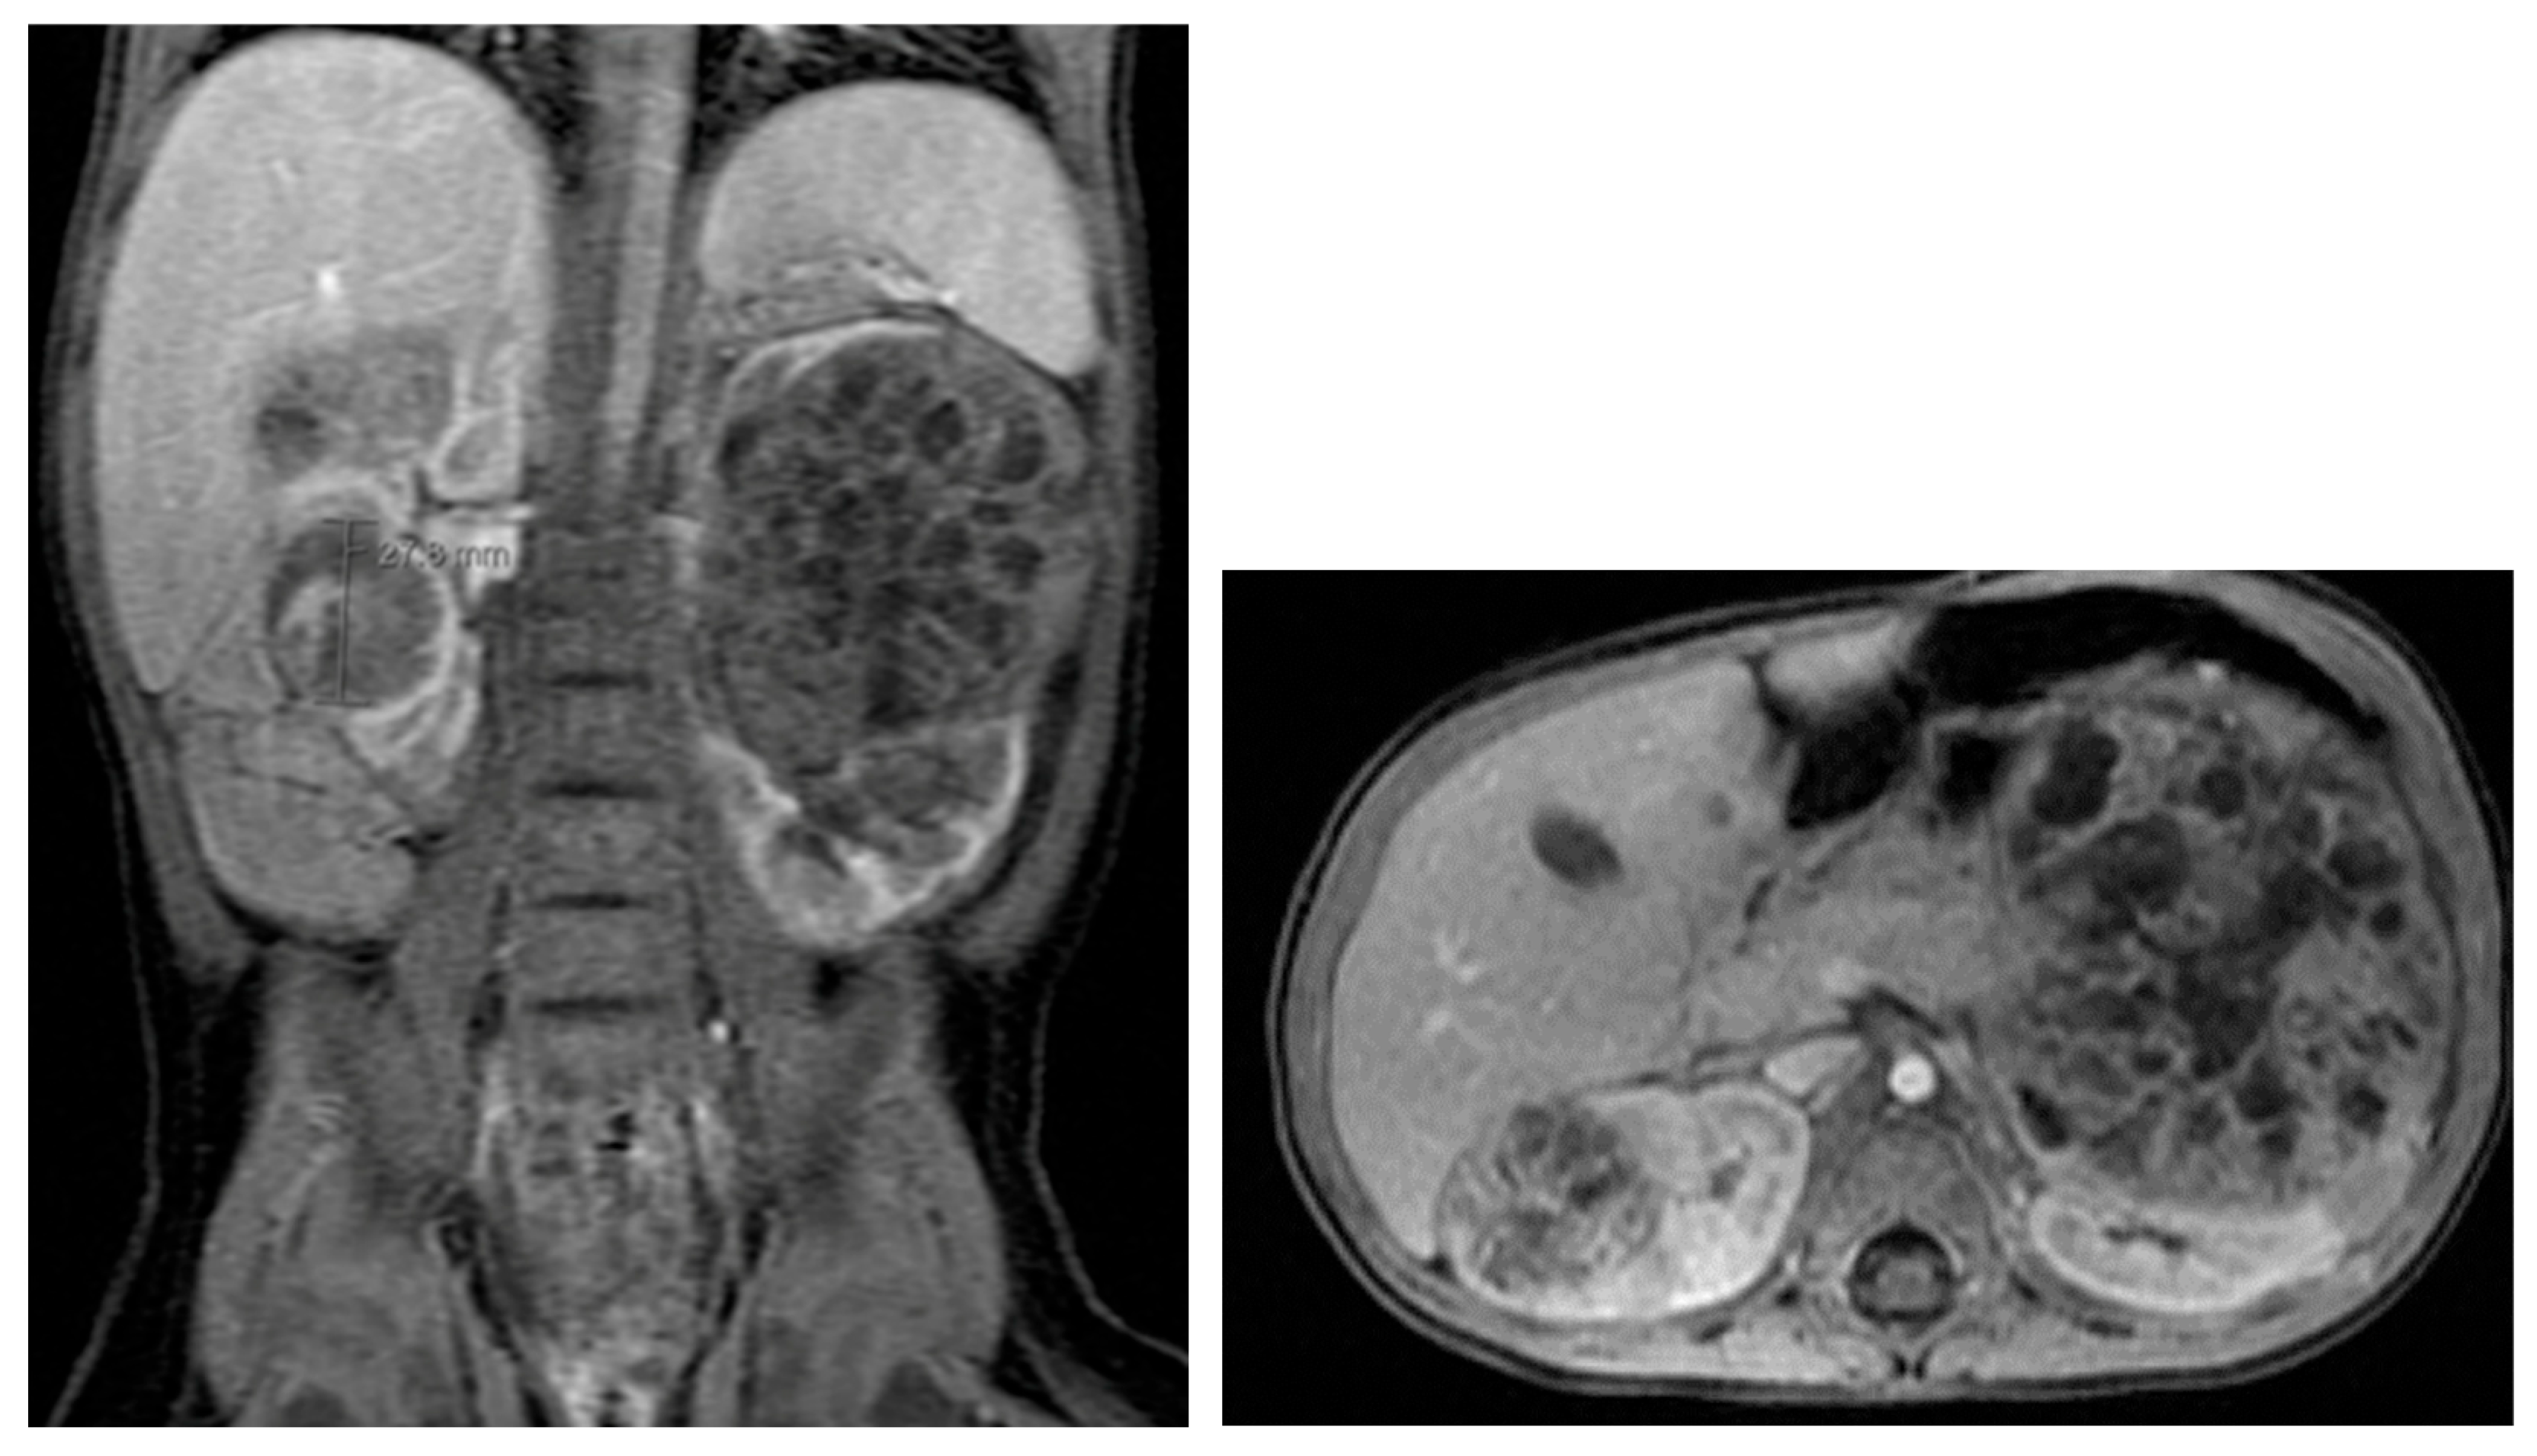

Autosomal dominant polycystic kidney disease (ADPKD) is marked by multiple cysts in both kidneys. US, MRI, and CT are useful for detecting renal cysts and complications (Figure 19) [68]. Cysts may also be present in the liver, spleen, and pancreas. The number and size of renal cysts in children increase with age [69]. Renal failure due to ADPKD is rare in children [70,71]. In adults, MRI is used to assess renal size and predict functional decline [68].

Figure 19. Autosomal dominant polycystic kidney disease in a 16-year-old female.

Medicina 61 00696 g019